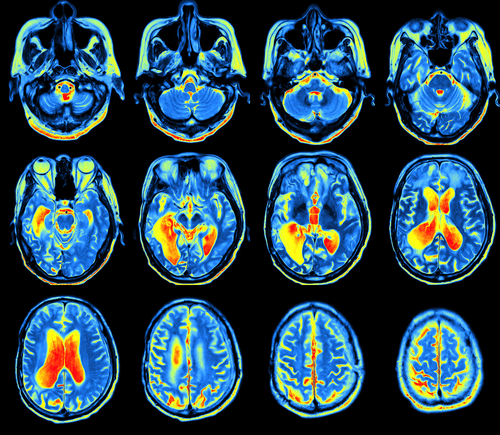

Protony mają również zastosowanie w diagnostyce obrazowej wykorzystywanej np. do wczesnego wykrywania zmian nowotworowych w ośrodkowym układzie nerwowym (spektroskopia magnetycznego rezonansu jądrowego, NMR) oraz w terapii chorób nowotworowych (radioterapia protonowa).